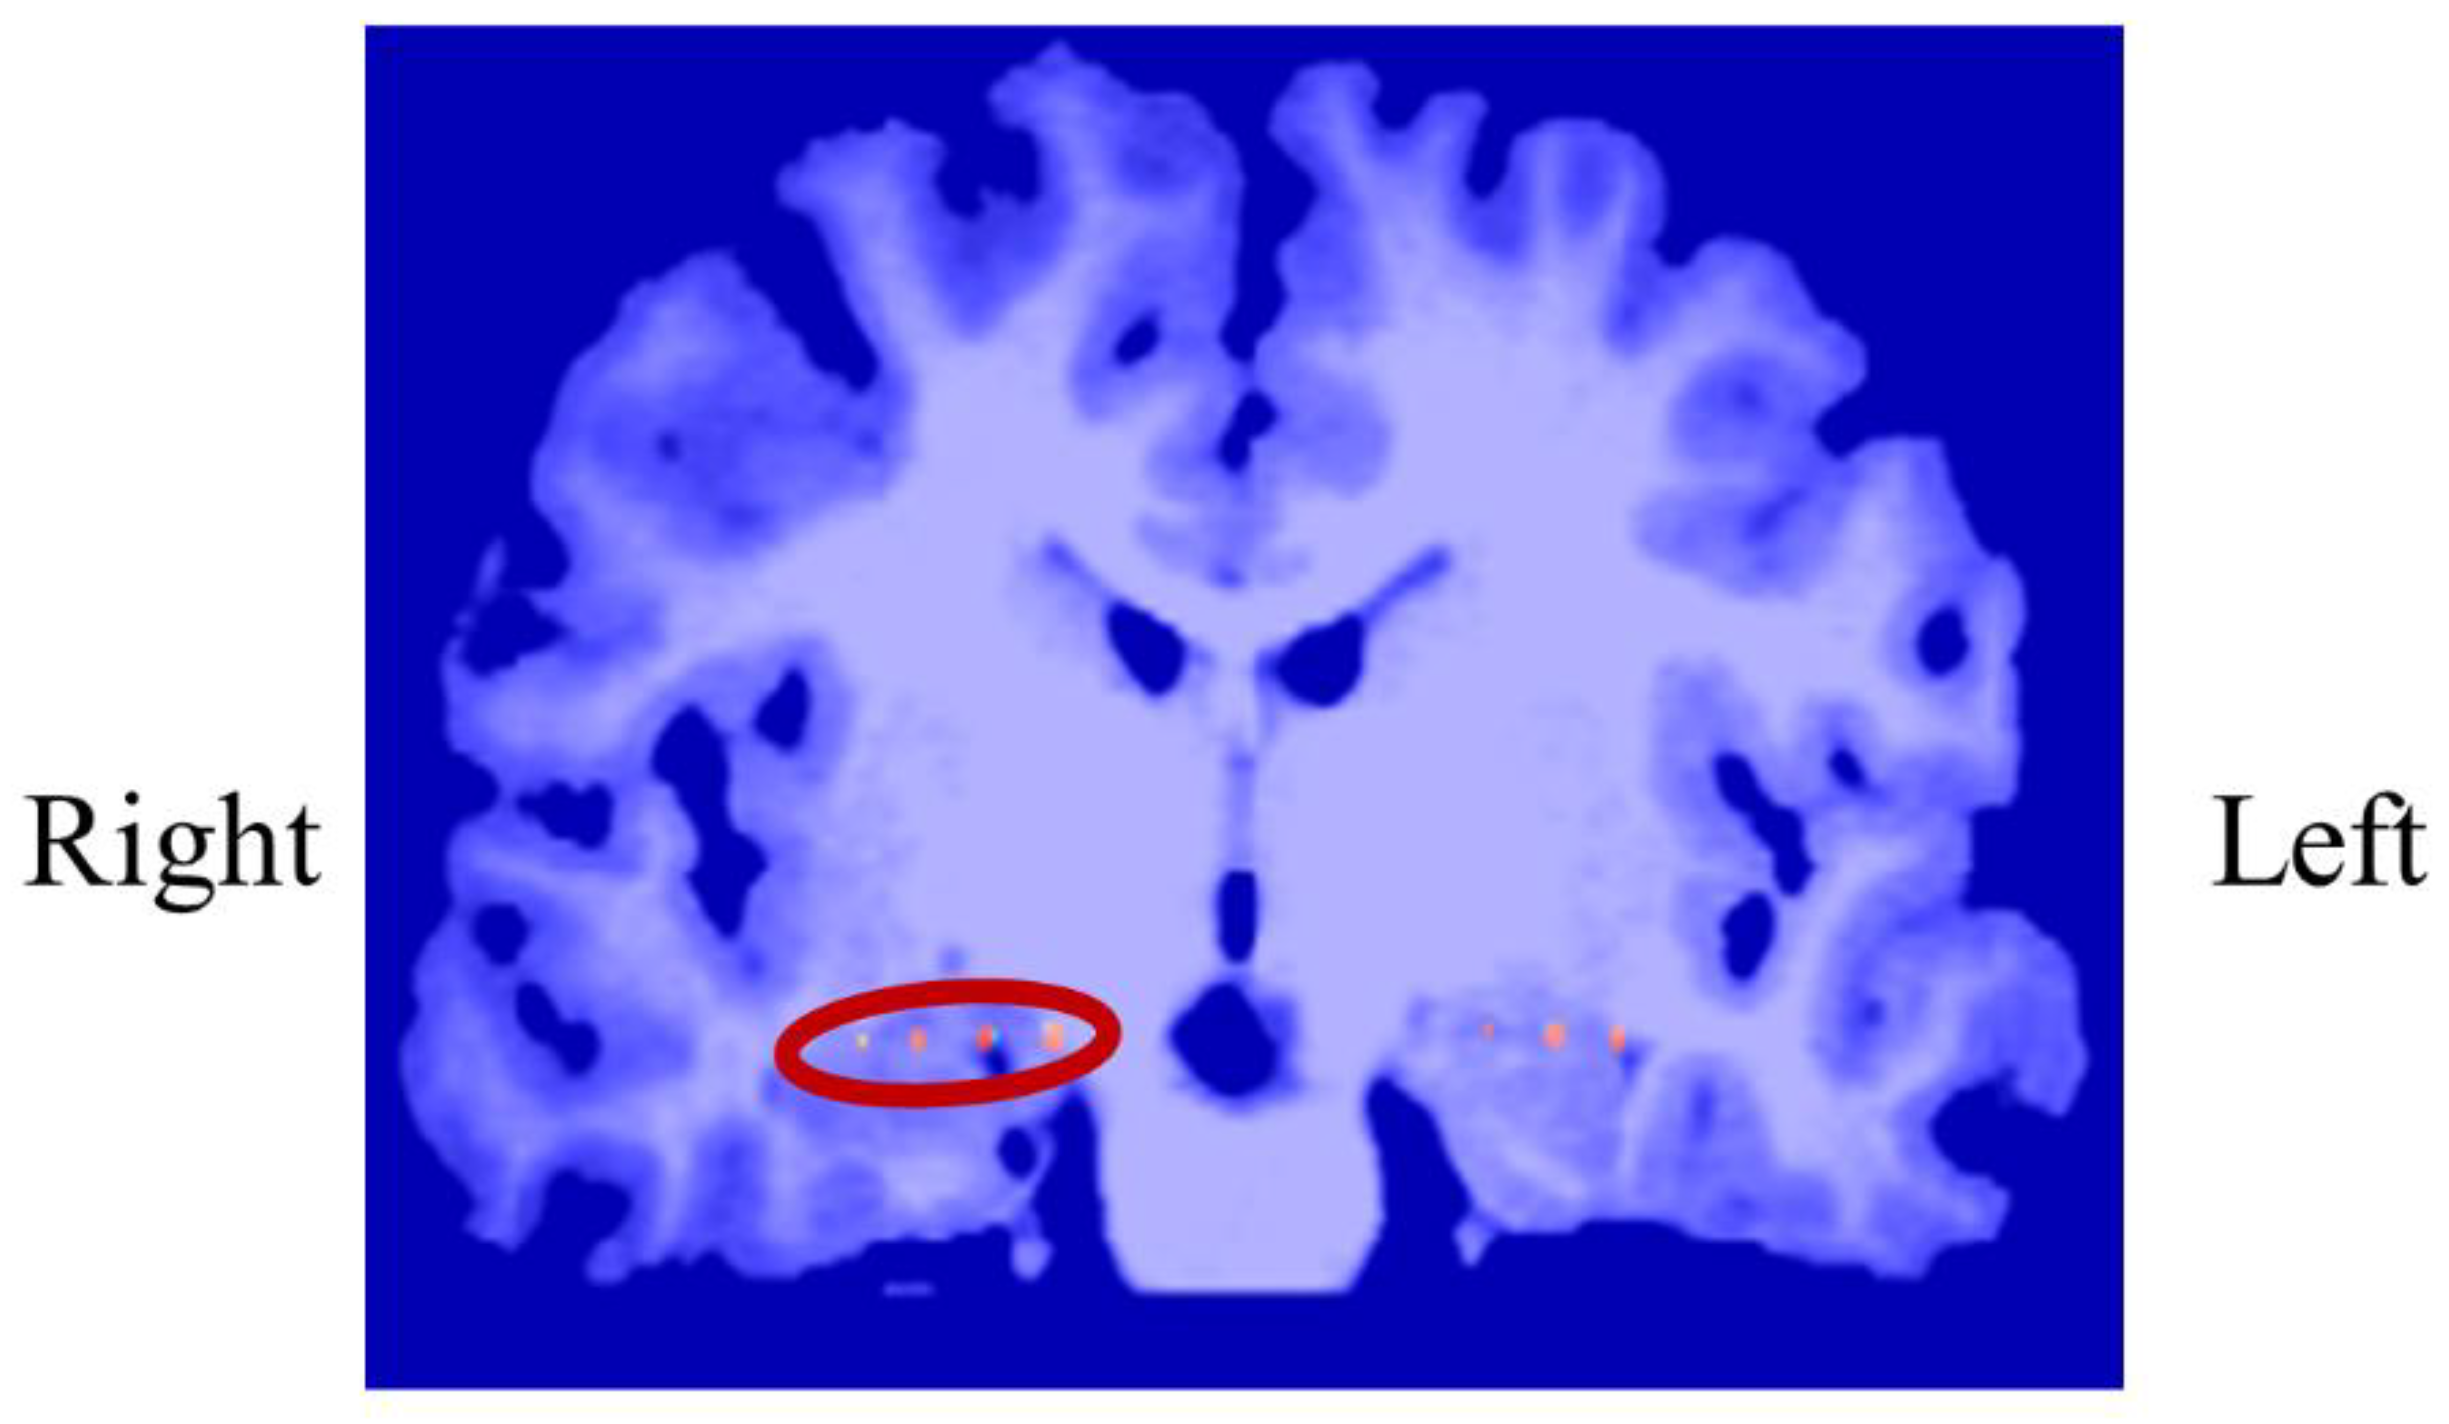

3.1.1. Intracranial Electrodes Used for Memory NF (P01)

In P01, deep electrodes (Unique Medical, Tokyo, Japan) were implanted in the right MTL. The iEEG data were measured from four platinum electrodes (1mm in length), positioned at 5mm intervals (centre to centre) from the tip located in the right hippocampus, and used for NF (Figure 4). A reference electrode was placed subcutaneously on the right side for P01.